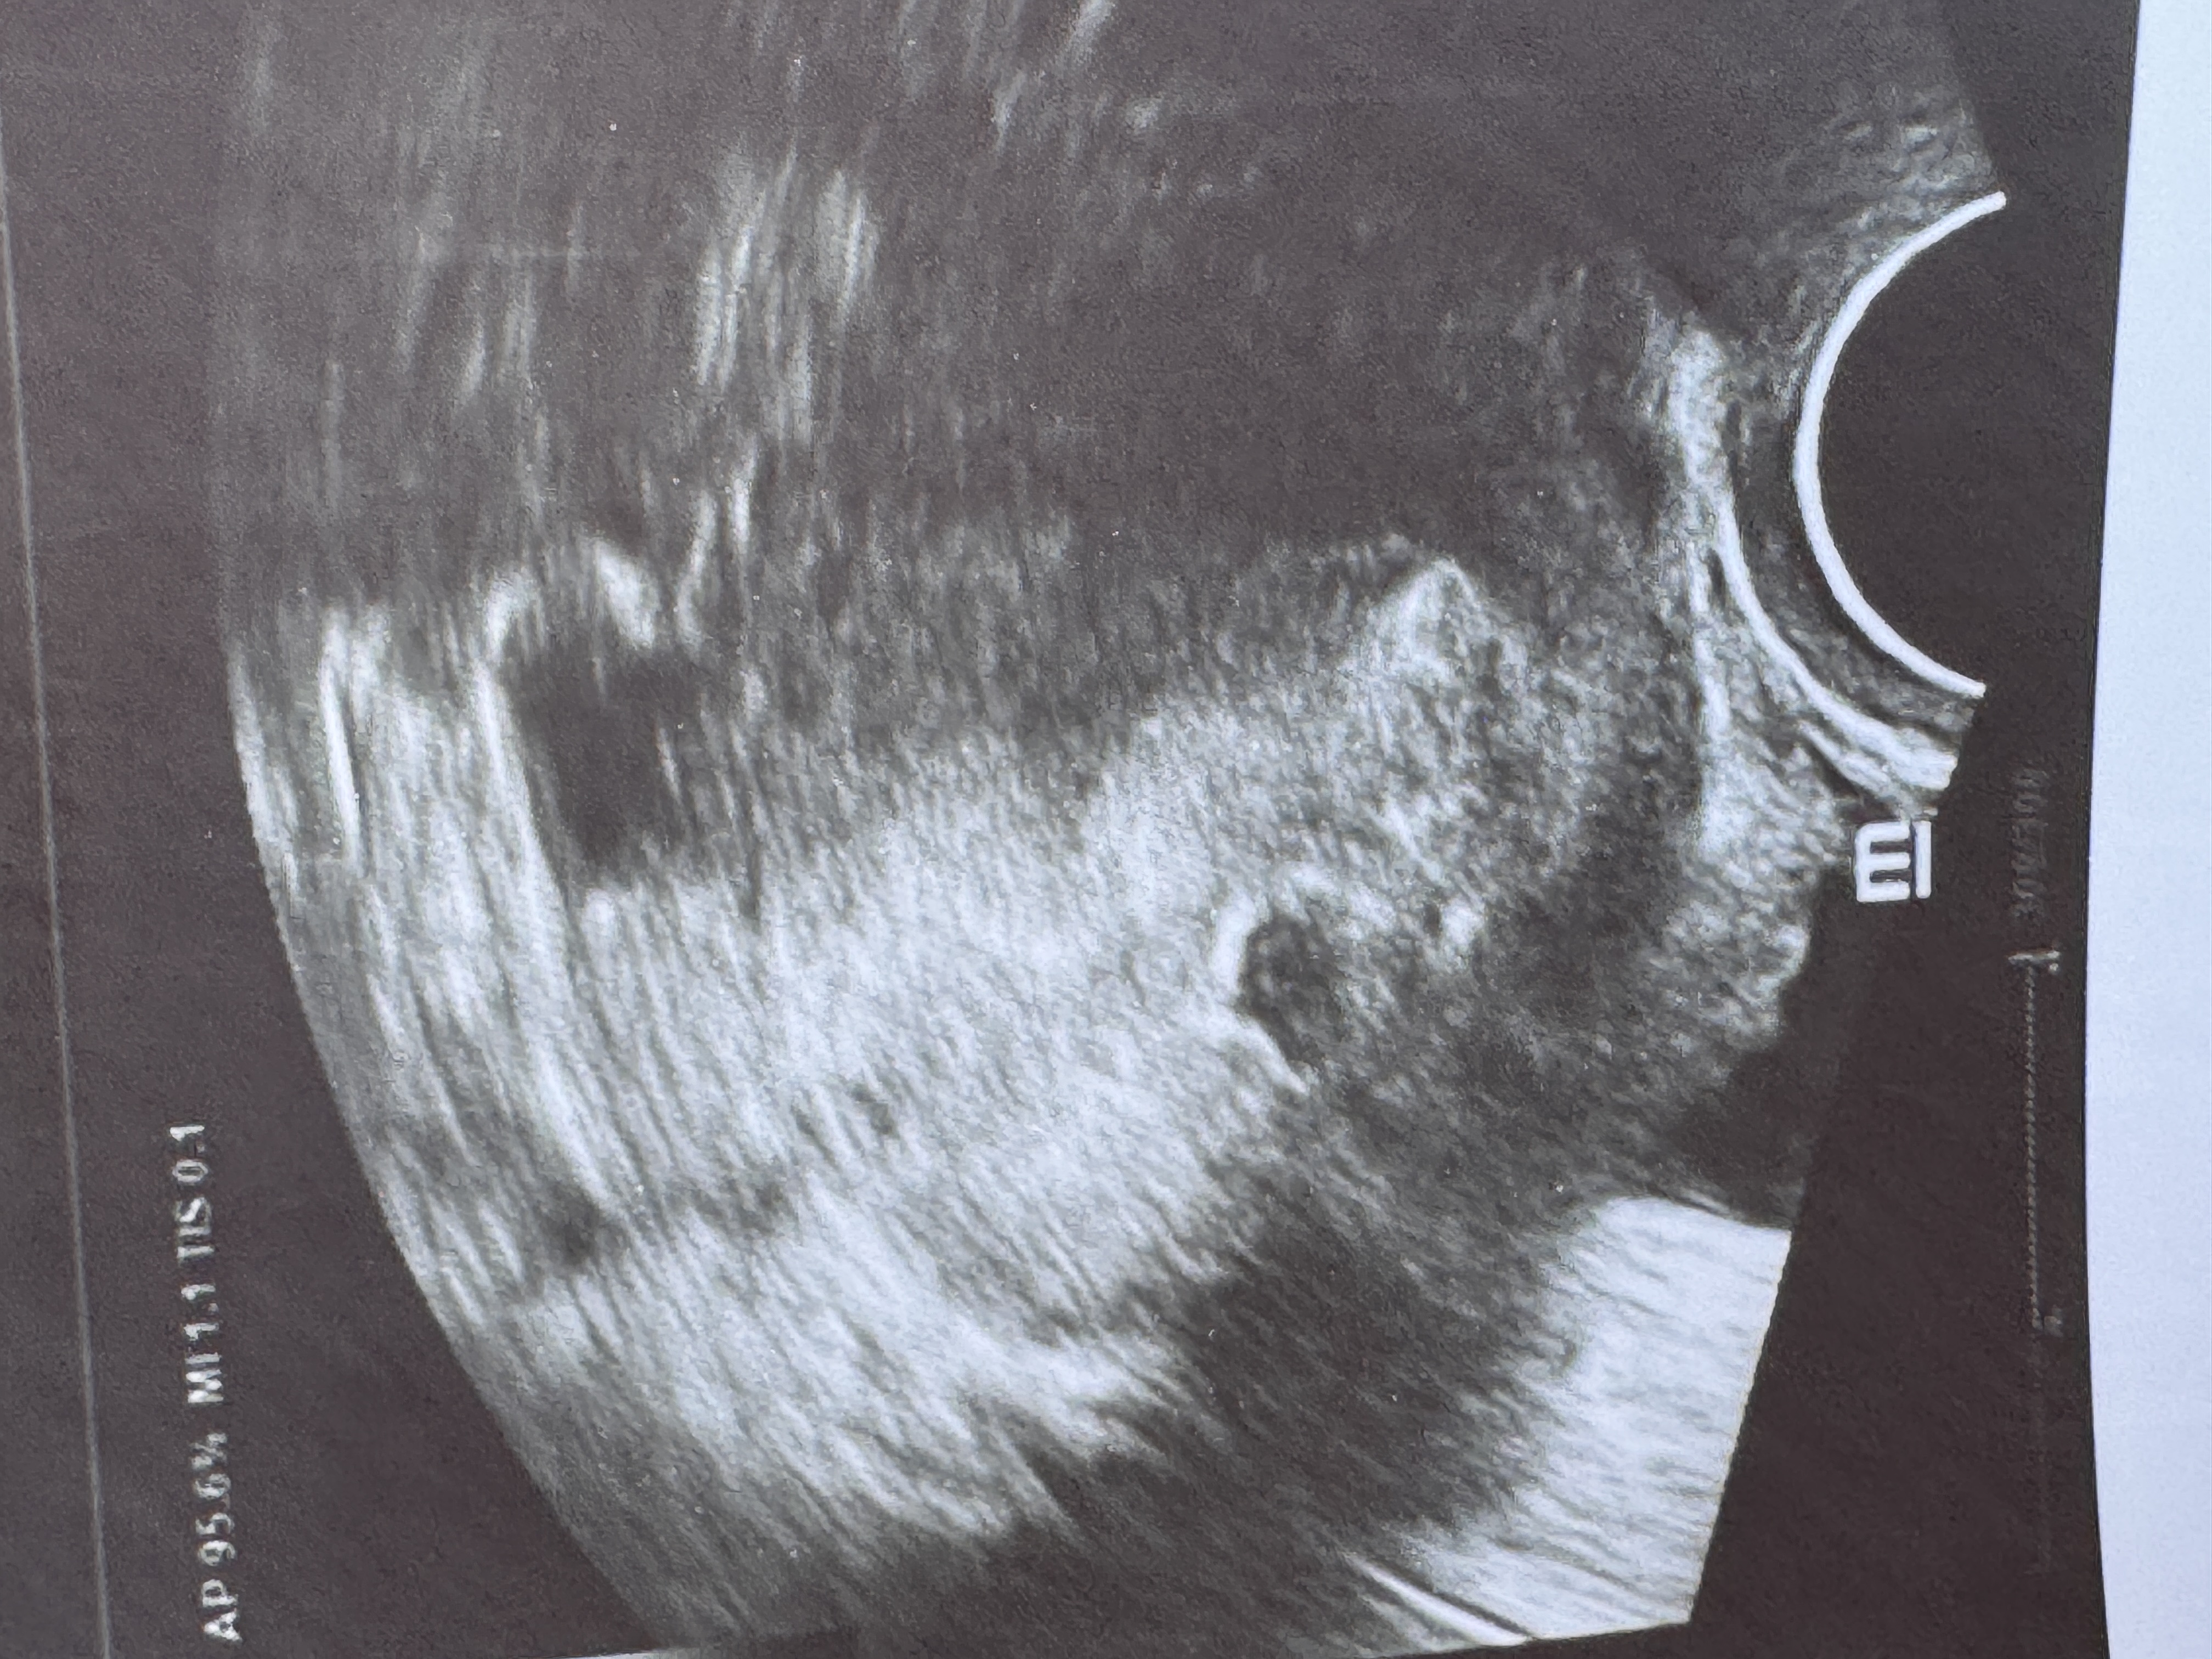

прохожу обследования. нашлись синехии, нужна гистероскопия( процесс затягивается…